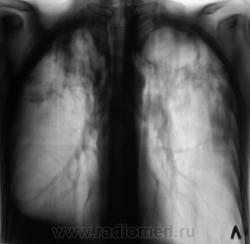

Мужчина, работает в областном центре, "в охране". Приехал проведать маму, так как мама заболела. На 3 день почувствовал себя "не очень" и решил обратиться в местную поликлинику к терапевту. В регистратуре выяснили, что мужчина в течение 3-х лет профилактическую флюорографию не проходил и направили во флюорографический кабинет.

Сразу-же, после производства флюорограммы, пациент был дообследован в рентгенодиагностическом кабинете согласно стандарту.

добрый день. мама как раз может и не болеть.а у ее сына хороший инфильтративный туб-з с распадом и обсеменением,но процесс не "свежий",есть объемное уменьшение в\д справа,нет перикавитарной инфильтрации,но активный. из вновь приобретенной патологии-экссуд.плеврит справа. немного удивляет:б-ой из области,скорее всего "обязательный контингент" ,и рфо более 3лет.иногда из иту приходят с меньшими процессами. в мокроте нашли куб?

1. Я выставил без "всяких" фиброзно-кавернозный. Далее коллеги-фтизиатры разберутся.

Фтизиатры согласились с ФКТ, палки при микроскопии - море.